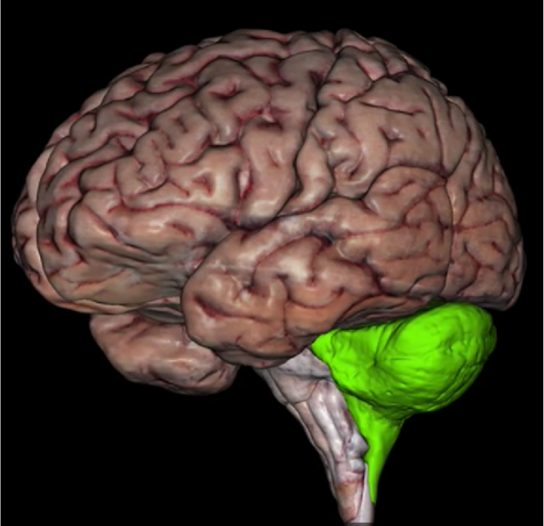

What is this?

Cerebellum